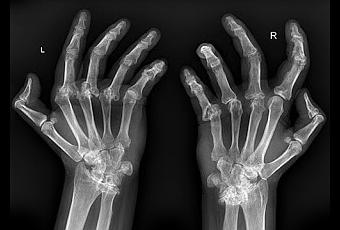

Esta enfermedad reumática puede afectar a la cadera, la zona lumbar y la cervical, pero este mal suele localizarse sobre todo en la rodilla y en la mano. La artrosis impide realizar rutinas cotidianas como caminar o abrir y cerrar la mano. La obesidad y la falta de ejercicio físico propician la aparición de esta enfermedad crónica que se puede combatir con unos hábitos de vida saludables como practicar algún deporte y mantener una dieta equilibrada.

Es más común que lo padezcan las mujeres, y sus síntomas comienzan a notarse desde los 20 hasta los los 50 años de edad. Según la Organización Mundial de la Salud (OMS), las enfermedades reumáticas , como la artrosis, supondrán la principal causa de discapacidad en 2020.La artrosis se produce por el desgaste del cartílago que une los huesos y permite el movimiento de las articulaciones. Una vez que aparece, sus síntomas de quedan para toda la vida. Se puede retrasar el proceso con una serie de hábitos y tomar analgésicos en los momentos de más dolor. También se puede recurrir a la operación de la zona afectada con el implante de una prótesis de silicona en lugar del cartílago desgastado.Esta enfermedad aparece con la edad de manera natural la edad, pero una artrosis patológica o dolorosa es causada por los esfuerzos, el sobrepeso y la genética. Uno de los remedios naturales más eficaces para combatir esta patología es el jengibre. Esta planta medicinal es un antiinflamatorio natural que no solo ayudará a adelgazar, si no que también ayudará a combatir enfermedades respiratorias, diabetes y problemas digestivos.